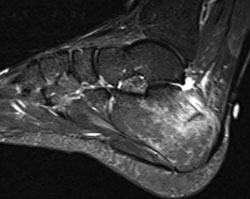

Calcaneus stress fracture

Calcaneus (heel bone) stress fracture